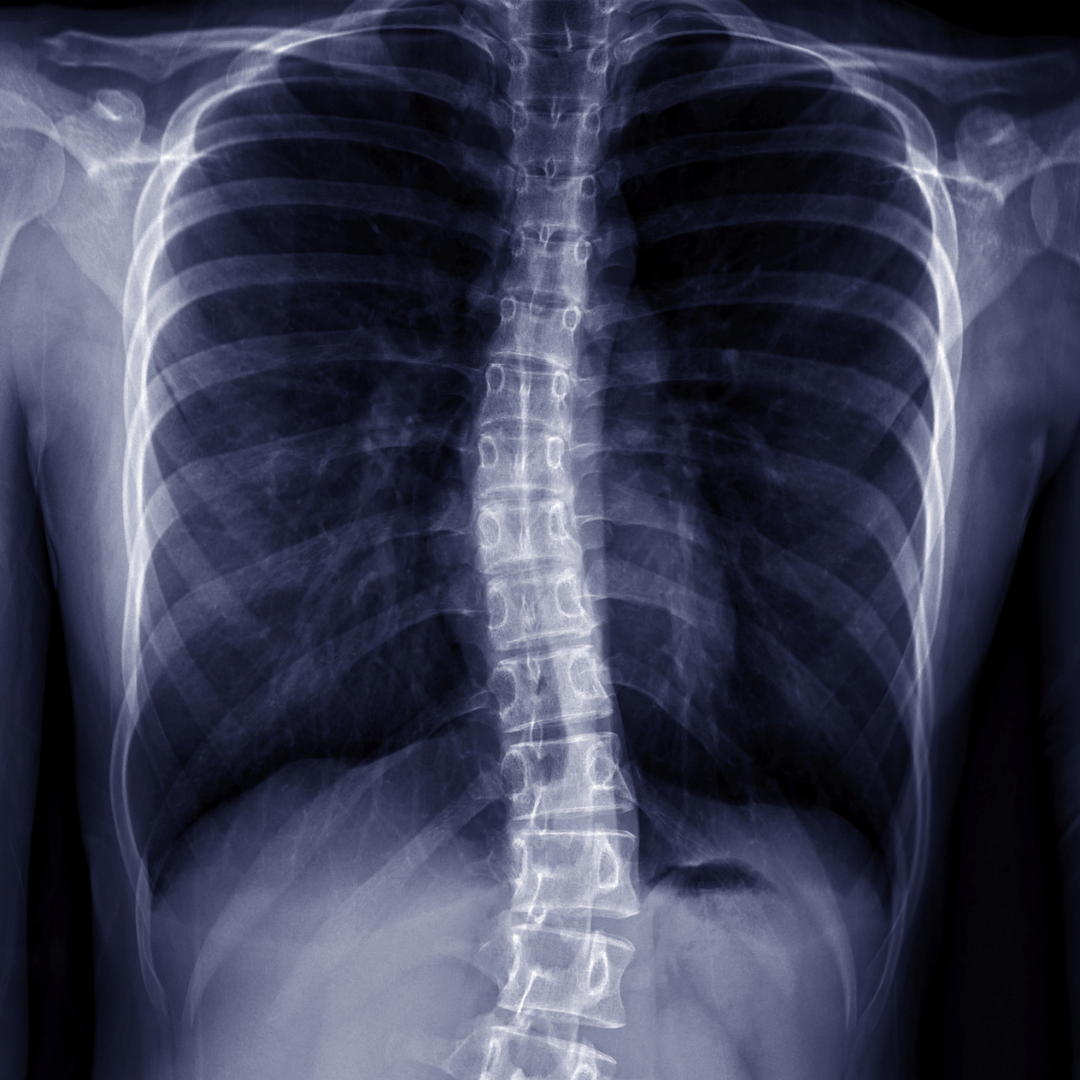

Scoliosis

Scoliosis is a condition of abnormal sideways curvature of the spine.

When scoliosis is suspected an x-ray may be required. Measurements are used to grade the severity.

It is important to identify scoliosis early, especially in the teenage years, and around periods of growth.